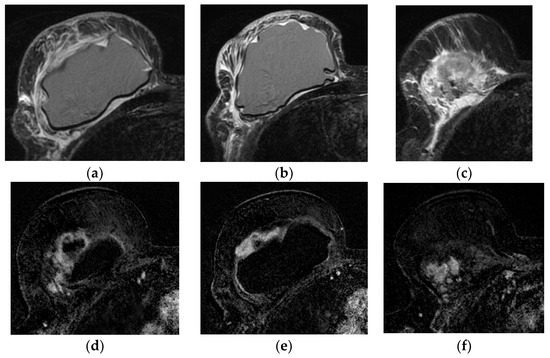

5.2.5. Implant Rupture

- Wong, T.; Lo, L.W.; Fung, P.Y.; Lai, H.Y.; She, H.L.; Ng, W.K.; Kwok, K.M.; Lee, C.M. Magnetic resonance imaging of breast augmentation: A pictorial review. Insights Imaging 2016, 7, 399–410. [Google Scholar] [CrossRef] [PubMed]

- Norena-Rengifo, B.D.; Sanin-Ramirez, M.P.; Adrada, B.E.; Luengas, A.B.; Martinez de Vega, V.; Guirguis, M.S.; Saldarriaga-Uribe, C. MRI for Evaluation of Complications of Breast Augmentation. Radiographics 2022, 42, 929–946. [Google Scholar] [CrossRef]

- Green, L.A.; Karow, J.A.; Toman, J.E.; Lostumbo, A.; Xie, K. Review of breast augmentation and reconstruction for the radiologist with emphasis on MRI. Clin. Imaging 2018, 47, 101–117. [Google Scholar] [CrossRef]

- Seiler, S.J.; Sharma, P.B.; Hayes, J.C.; Ganti, R.; Mootz, A.R.; Eads, E.D.; Teotia, S.S.; Evans, W.P. Multimodality Imaging-based Evaluation of Single-Lumen Silicone Breast Implants for Rupture. Radiographics 2017, 37, 366–382. [Google Scholar] [CrossRef] [PubMed]

| Rupture * | Implant shell | Intact fibrous capsule | Intracapsular |

| Implant shell and fibrous capsule | Extracapsular | ||

| Definitive rupture | Linguini sign | Low signal lines within the silicone |

| Subcapsular lines | Low signal lines parallel to the capsule surrounded by silicone | |

| Free Silicone | Extracapsular silicone | |

| Possible rupture | Keyhole or teardrop Sign | Focal silicone invagination between implant shell and fibrous capsule |

| Salad-oil sign Rat-tail sign | Silicone gel mixed with peri-implant fluid Contour irregularity extending along the chest wall | |

| Pitfalls | Complex radial folds | Long invaginations of the shell |

| Gel bleed | Silicone within the axillary lymph nodes | |

| Double-lumen implant | Inner compartment shell may mimic intracapsular rupture |